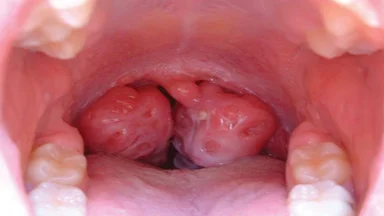

Viêm họng hạt là tình trạng màng nhầy phía sau cổ họng hoặc hầu bị viêm. Điều này xảy ra khi bệnh nhân bị viêm họng kéo dài nhưng không được điều trị dứt điểm. Viêm họng hạt sẽ gây khó chịu, khô họng và khó nuốt, ảnh hưởng nghiêm trọng đến sức khỏe người bệnh. Theo thống kê, bệnh lý này có thể xảy ra ở mọi lứa tuổi, ở mọi giới tính nhưng gặp nhiều nhất ở những người có hệ miễn dịch yếu, cơ thể hay bị suy nhược và tiến triển khi thời tiết trở lạnh.

– Có hạt sưng ở cổ họng nên có cảm giác ngứa ngáy hoặc vướng ở họng.